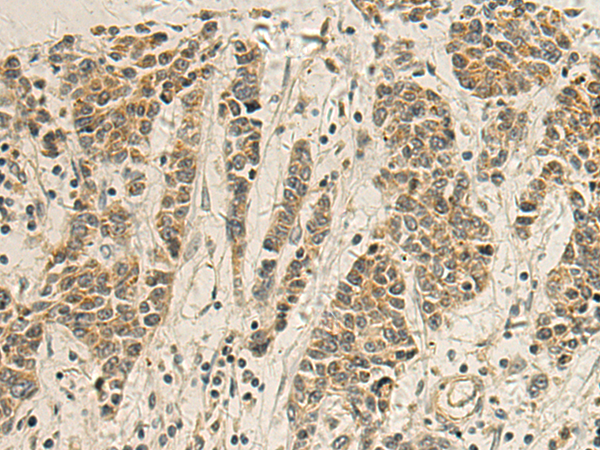

The image is immunohistochemistry of paraffin-embedded Human colorectal cancer tissue using P03519(GSDMA Antibody) at dilution 1/115. (Original magnification: ×200) |